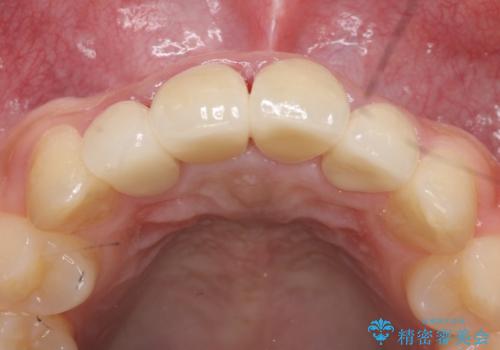

- 上顎前歯の歯並びが気になるが仕事が忙しく矯正治療は難しいため、セラミック矯正で綺麗にしたいといらっしゃった方の症例です。

左右の1番目の歯は傾きが大きいため、セラミッククラウンにするにあたり神経治療を行うことを御了承頂いた上で、前歯4本をオールセラミッククラウン(スペシャル)により補綴しました。

前歯の補綴ではオールセラミッククラウンを希望される患者様が多いですが、オールセラミッククラウンの中でも、エコノミー、スタンダード、スペシャル、エクセレントとランクがあります。

その中でも特に審美性が高いのがスペシャル、エクセレントです。スペシャル、エクセレントは口腔内写真をもとに熟練の技工士が、患者様の口腔内に合わせたオーダーメイドのクラウンを製作致します。